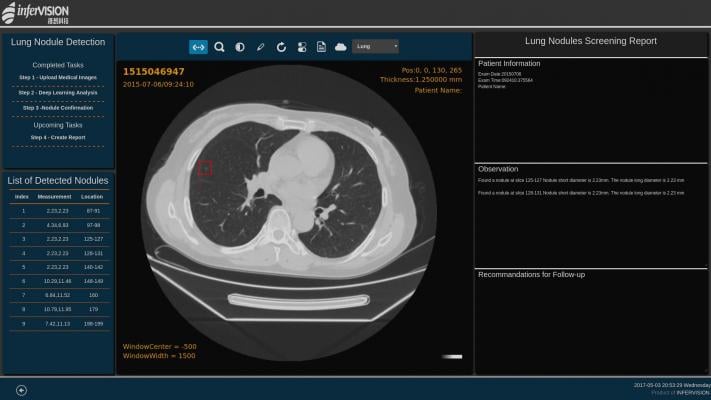

USPSTF guidelines call for computed tomography (CT) screening only of adults between ages 55 and 80 with a 30 pack-year smoking history who either smoke or have quit within the past 15 years.